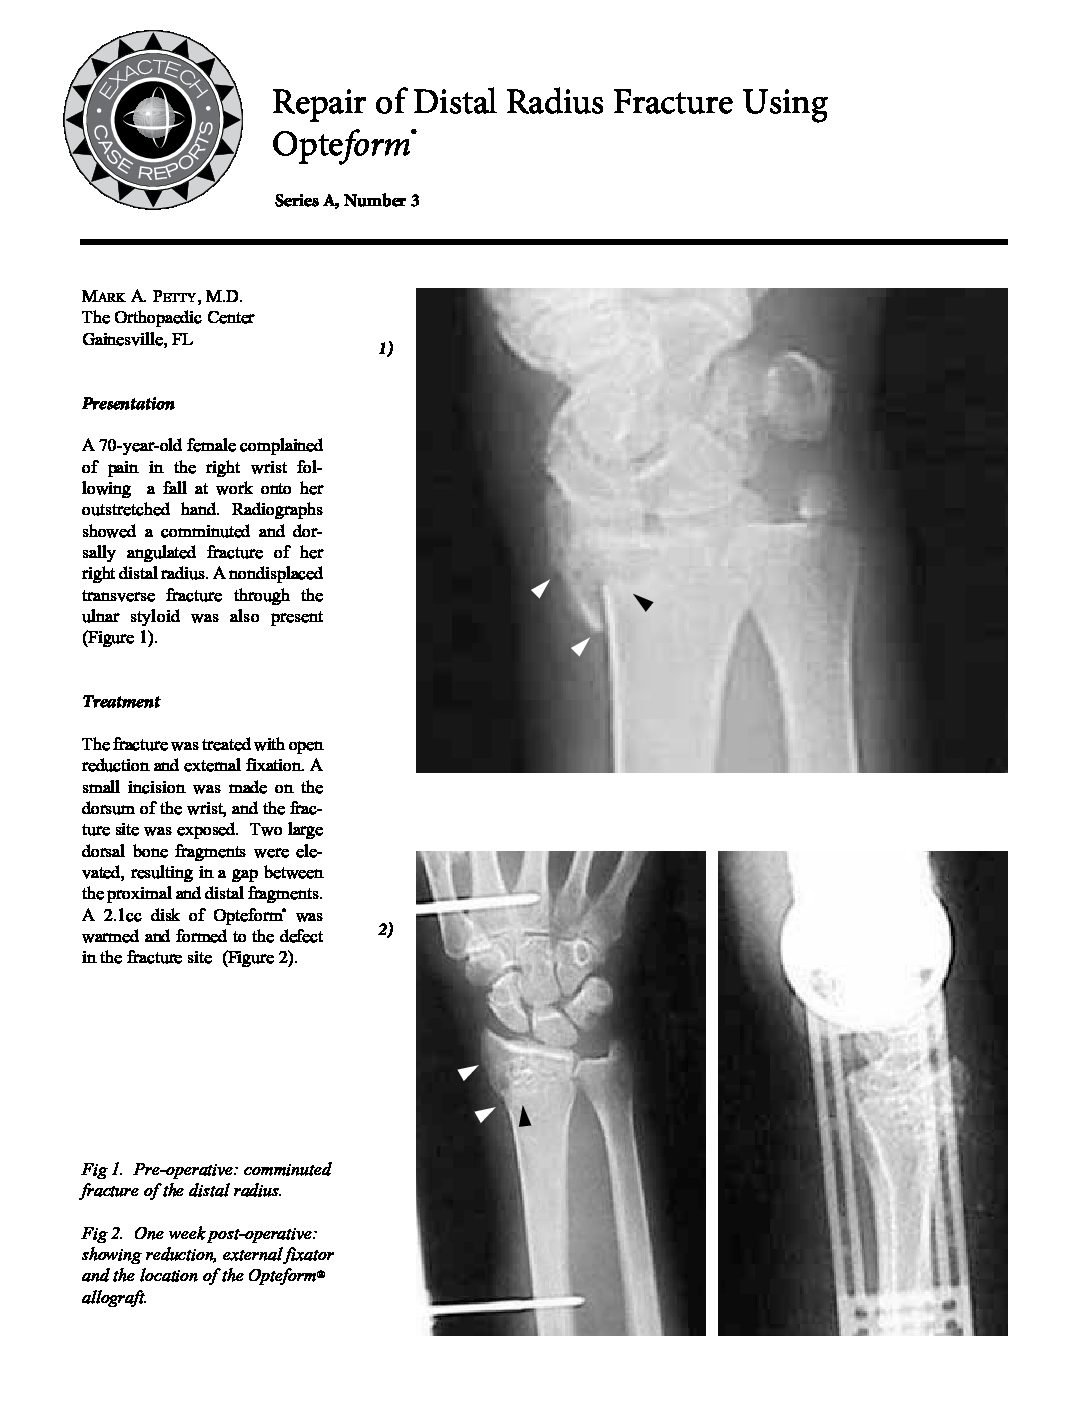

From www.exac.com